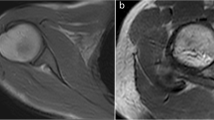

The constructed array was electrically characterised and the reproducibility of the cyclic motion was validated. Snapshots of dynamic in vivo images taken at a temporal resolution (308 ms) are presented. Some of the fine internal structures within the minipig’s knee, like cruciate ligaments, are traced in the snapshots.

This study is a step towards making dynamic imaging which can give additional information about joint injuries when static MRI is not able to give sufficient information, a routine clinical application. There, the combination of a high-density receive array and a movement device will be highly helpful in the diagnosis and therapy monitoring of knee injuries in the future.